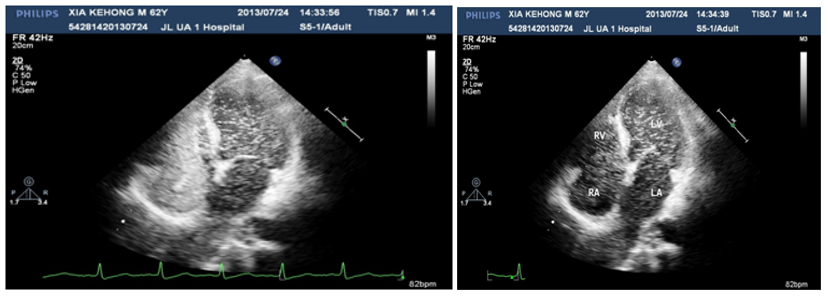

A 60years old male, known case of diabetes mellitus, hypertension and alcoholic hepatic cirrhosis had exercise induced chest discomfot, shortness of breath, fatigue and lips cyanosis half a year ago, which relieved at rest. But later he became serious for one week and visited our department for further management. He had no cough, fever, dizziness, headache or bleeding history from any site. He had pituitary adenoma, which was surgically removed 6years ago. He denies history of chronic infections such as tuberculosis or actinomycosis or family history of hereditary hemorrhagic telangiectasis (HHT). Physical examination revealed cyanosis of the face and lips, clubbing, numerous spider naevi on neck, chest and palm and no telangiectasia on mucosa or fundi. His blood pressure was 130/80mmHg, heart rate was 76beats/min and resting oxygen saturation was 66% in room air. A grade 1/6 soft systolic murmur was heard on the upper left sternal border and clear lungs sound. There were no bruits. The hemoglobin was 11.5gm/dL and the hematocrite was 35.5gm/dL. Arterial blood gas analysis showed Pao2 64mmHg on room air and after 100% of oxygen 74mmHg with Paco2 41mmHg and PH-7.35. Chest radiography and electrocardiogram did not show any abnormalities. Pulmonary function test showed alveolar dispersion function severely reduced. Transthoracic echocardiography showed normal findings (No PFO/ASD/VSD/PDA detected). We performed contrast echocardiography using agitated saline. A delayed appearance of a substantial amount of micro-bubbles in the left atrium greater than three cardiac cycles after appearance in the right atrium and ventricle (Figure 1) which was suggestive of pulmonary arteriovenous fistula. The delayed appearance and a large amount of micro-bubbles in the left atrium preclude the intracardiac shunting resulting from a patent foramen ovale (PFO) or arterial septal defect (ASD). Interestingly, the density of micro-bubbles was the same in the left and right cardiac chamber even after 10 cardiac cycles (Figure 2 & 3) and when the injection stopped, there were micro-bubbles in the left cardiac chambers meanwhile none in the right cardiac chambers (Figure 4). Because the hepatic function of the patient was in compensatory period, we gave him oxygen-inhalation and beta-blockers in order to decrease the oxygen demands and to lower the portal vein pressure. Moreover, he was advised to avoid sudden standing. The cyanosis improved, and the patient was discharged from the hospital and on regular follow-up. The patient was advised for pulmonary angiography but refused.

Figure 2&3 The density of micro-bubbles was the same in the left and right cardiac chambers even after 10 cardiac cycles.